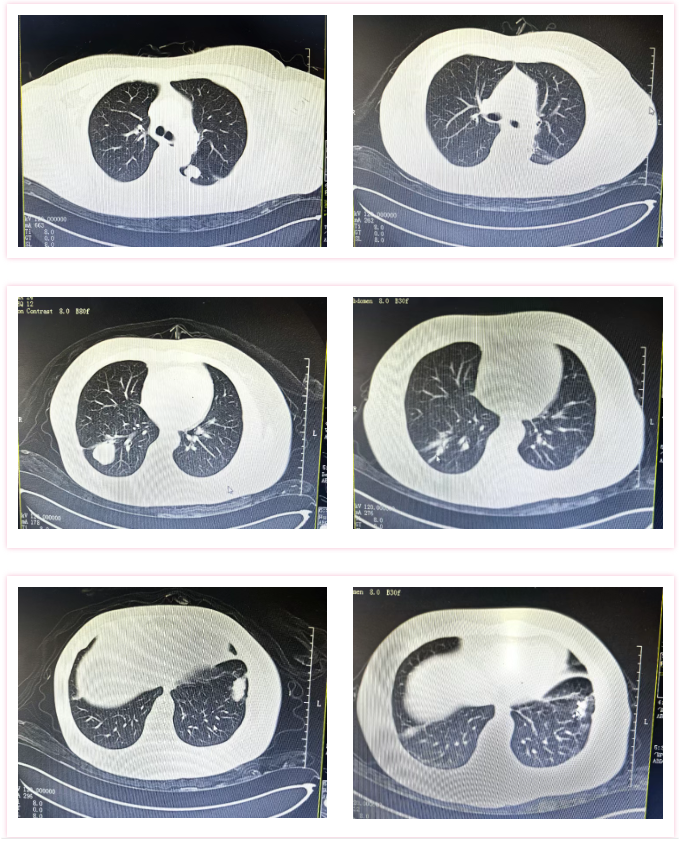

“双肺多发转移瘤,临近右下肺动脉、叶间胸膜、胸壁胸膜粘连……”针对李姐的病情,医疗团队先后为她实施了2次肺转移瘤冷冻消融术,并同步穿刺活检,活检结果再次证实为:原宫颈癌转移。

△三次碘粒子植入前(左图)后(右图)对比